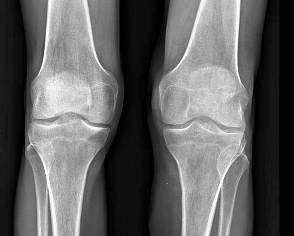

Al Rayos X. de ambas rodilla se aprecia aumento de volumen de las partes blandas de la rodilla y pantorrilla izquierda.

Se observan quistes subcondrales en rodilla izquierda.

Rayos X ambas rodillas con aumento de volumen de las partes blandas de la rodilla y pantorrilla izquierda. Se observan quistes subcondrales en rodilla izquierda. Imagen 4

Imagen 4. Rayos X ambas rodillas donde se observa aumento de volumen de las partes blandas